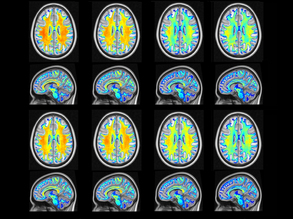

Busybody...Fitter Brain